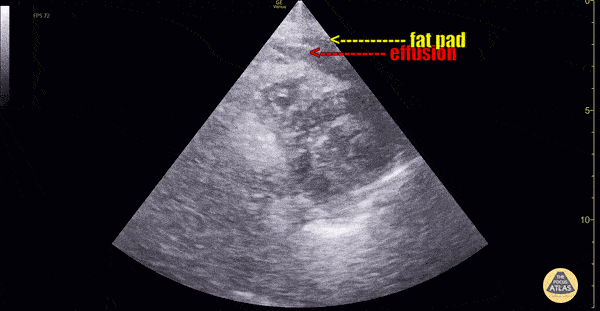

Pericardial fat pad is often mistaken for a pericardial effusion, this clip demonstrates both in the same clip. Pericardial fat pad moves in concert with the heart, while an effusion is circumferential, stationary and does not move in concert with the heart. Multiple cardiac views are helpful in making the diagnosis. Dr. Dimitri Livshits Ultrasound Fellow;Dr. Jane Belyavskaya Ultrasound Fellow;Dr. Chris Hanuscin Ultrasound Fellowship Director